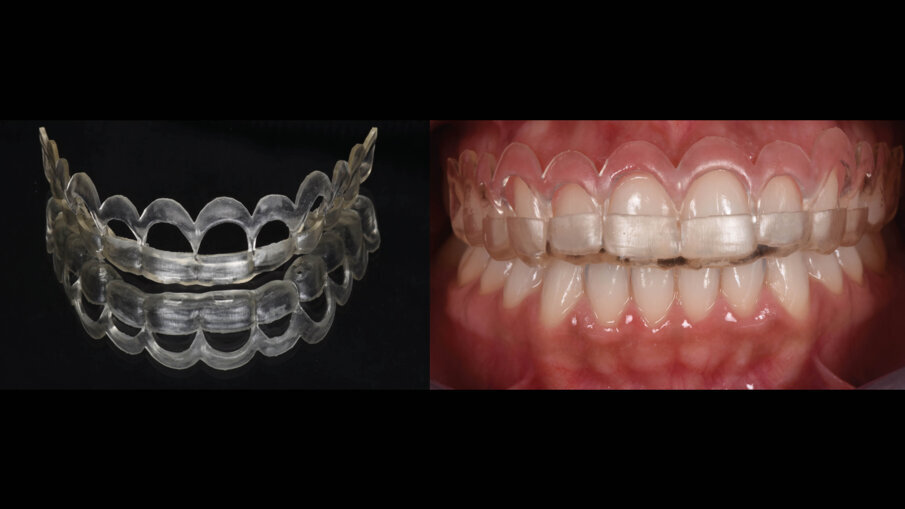

Il software consente di vedere e apprezzare la simulazione nelle diverse visioni agevolando la pre-visualizzazione sia al clinico che al paziente (Figg. 7-9). Questa progettazione consente di modellare e stampare con una stampante 3D una guida chirurgica che agevolerà la chirurgia prima mucogengivale e poi resettiva nei casi in cui fosse necessaria (Fig. 10). La guida chirurgica viene stampata e spedita allo studio e il paziente viene convocato per la prova pre-chirurgica (Fig. 11). La guida ha una “finestra” interna che definisce l’entità della gengivectomia atta a esporre lo smalto del dente coperto dai tessuti molli, la parte superiore festonata serve invece come guida per regolare la nuova posizione della cresta ossea definendo la nuova dimensione di attacco sopra crestale che dovrebbe essere nel range di 2-3 mm.

Fig. 11_Prova pre-chirurgica su paziente.